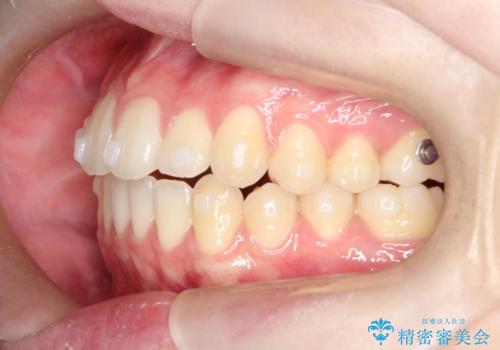

- 前歯のガタガタを主訴に来院されました。

開咬ぎみであったため、しっかりと前歯が噛むように計画を立てて治療をおこないました。

仕上がりも良く、患者様にも満足していただきました。